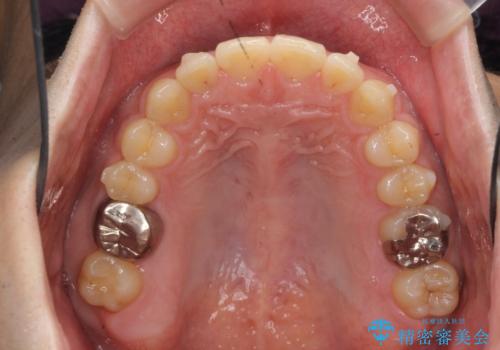

- 前歯の噛み合わせが反対になっていること、前歯の見た目の改善を希望され来院されました。

詳細な矯正検査の結果、顎の歪みが見られたため大きく歯を動かす治療ではなく前歯を主に並べることで前歯の前後関係を改善していきます。

前歯を主に動かす部分矯正であることからマウスピース矯正インビザラインによる治療を計画します。